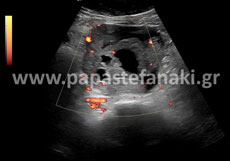

Με την έγχρωμη υπερηχοτομογραφία (Triplex) μπορούμε να ελέγχουμε την ροή του αίματος μέσα στα αγγεία του σώματος όπως η αορτή, οι καρωτίδες, οι νεφρικές αρτηρίες, οι φλέβες και αρτηρίες άνω και κάτω άκρων

Triplex Αγγείων

Τα Τriplex αγγείων (φλεβών και αρτηριών), που πραγματοποιούνται είναι τα εξής :